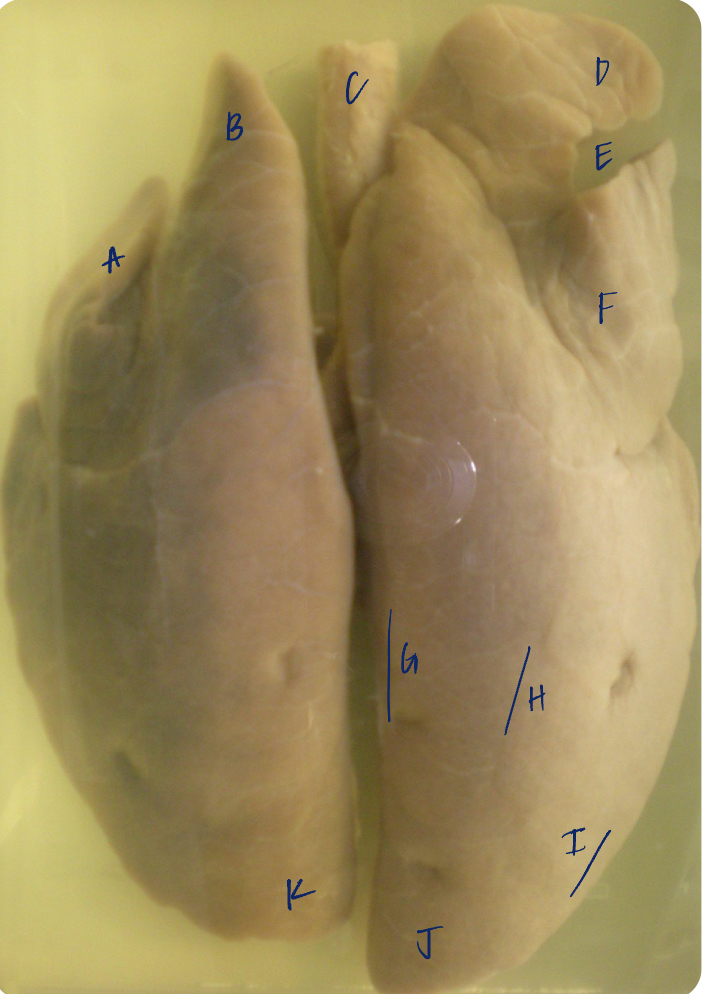

A

(cat larynx/trachea/lungs, dorsal)

epiglottis

B

(cat larynx/trachea/lungs, dorsal)

larynx

C

(cat larynx/trachea/lungs, dorsal)

trachea

D

(cat larynx/trachea/lungs, dorsal)

R cranial lobe

E

(cat larynx/trachea/lungs, dorsal)

middle lobe

F

(cat larynx/trachea/lungs, dorsal)

R caudal lobe

G

(cat larynx/trachea/lungs, dorsal)

primary bronchi

H

(cat larynx/trachea/lungs, dorsal)

L caudal lobe

I

(cat larynx/trachea/lungs, dorsal)

L cranial lobe

J

(cat larynx/trachea/lungs, dorsal)

cricoarytenoideus dorsalis m

K

(cat larynx/trachea/lungs, dorsal)

thyroid

A

(cat larynx/trachea/lungs, dorsal)

epiglottis

B

(cat larynx/trachea/lungs, dorsal)

larynx

C

(cat larynx/trachea/lungs, dorsal)

trachea

D

(cat larynx/trachea/lungs, dorsal)

R cranial lobe

E

(cat larynx/trachea/lungs, dorsal)

middle lobe

F

(cat larynx/trachea/lungs, dorsal)

R caudal lobe

G

(cat larynx/trachea/lungs, dorsal)

primary bronchi

H

(cat larynx/trachea/lungs, dorsal)

L caudal lobe

I

(cat larynx/trachea/lungs, dorsal)

L cranial lobe

J

(cat larynx/trachea/lungs, dorsal)

cricoarytenoideus dorsalis m

K

(cat larynx/trachea/lungs, dorsal)

thyroid